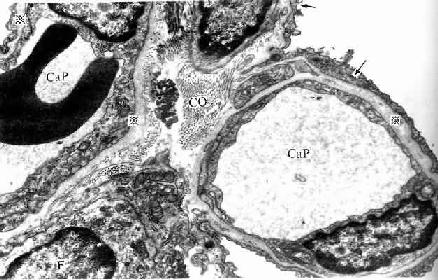

人肺泡隔电镜像

图14-15 人肺泡隔电镜像 ×13500

Cap毛细血管,F成纤维细胞,

CO胶原原纤维,※基膜,↑Ⅰ型肺泡细胞

(2)肺泡隔( alveolar septum):相邻肺泡之间的薄层结缔组织构成肺泡隔,属肺的间质。肺泡隔内含密集的毛细血管网,毛细血管为连续型,内皮甚薄,无孔,胞质内含较多吞饮小泡。隔的厚薄不一,弹性纤维较丰富,也有少量胶原纤维网状纤维,并有成纤维细胞巨噬细胞浆细胞肥大细胞等以及淋巴管神经纤维。隔内丰富的弹性纤维有助于保持肺泡的弹性,老年人弹性纤维退化炎症等病变也可破坏弹性纤维,使肺泡弹性减弱,肺泡渐扩大,导致肺气肿,肺换气功能减低。隔内的毛细血管大多紧贴肺泡上皮,上皮基膜与内皮基膜相互融合;有的部位的肺泡上皮与毛细管内有少量结缔组织(图14-15)。

(4)气血屏障(blood-air barrier):肺泡内气体与血液内气体分子交换所通过的结构称气血屏障。它由以下结构组成:肺泡表面液体层、Ⅰ型肺泡细胞与基膜、薄层结缔组织、毛细血管基膜与内皮。有的部位的肺泡上皮与血管内皮之间无结缔组织,两层基膜直接相贴而融合(图14-15)。气血屏障很薄,总厚度约0.5μm。间质性肺炎时,肺泡隔结缔组织水肿,炎症细胞浸润,以致肺气体交换功能障碍